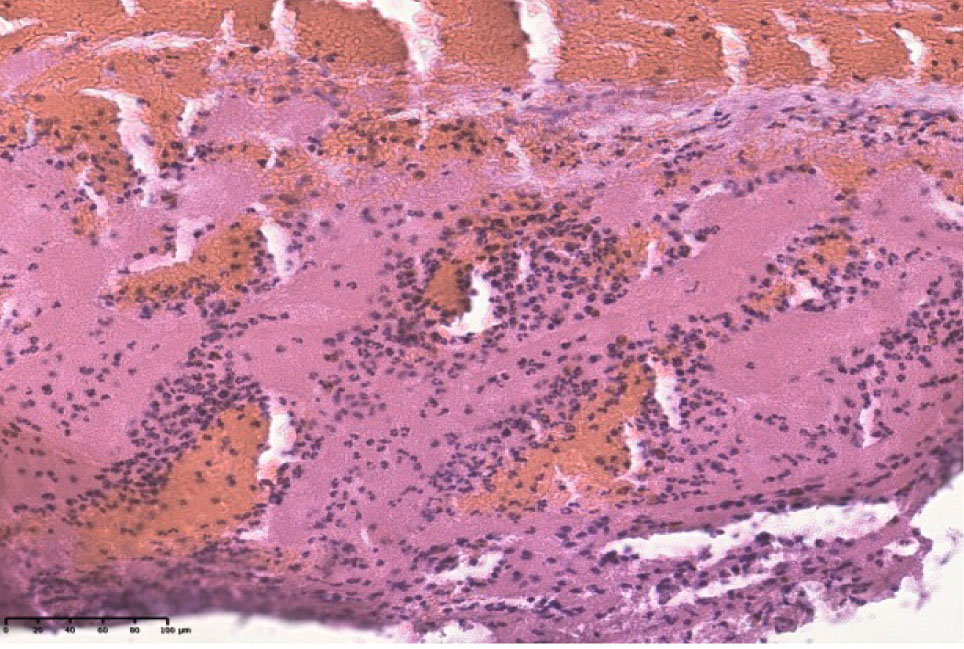

При повторном инфаркте миокарда в мышечных волокнах наблюдается значительное количество гипертрофированных кардиомиоцитов и гипотрофировавнных с отложениями зерен буро-коричневого цвета. Ярко выражены признаки кардиосклероза и кардиофиброза. В поле зрения визуализируются отечные мышечные волокна, лишенные поперечной исчерченности, гомогенезированые, ядра пораженных мышечных волокон сохранены, чаще пикноморфны. Наблюдаются кардиомиоциты в состоянии глыбчатого распада, участки некроза с пролиферацией клеток гистиои фибробластического рада. Кровеносные сосуды полнокровные (рис. 1Б).

Рис. 1. Срез стенки сердца мужчины 67 лет (инфаркт миокарда) (А). Срез стенки сердца женщины 65 лет (повторный инфаркт миокарда) (Б). Окрашено гематоксилином и эозином.